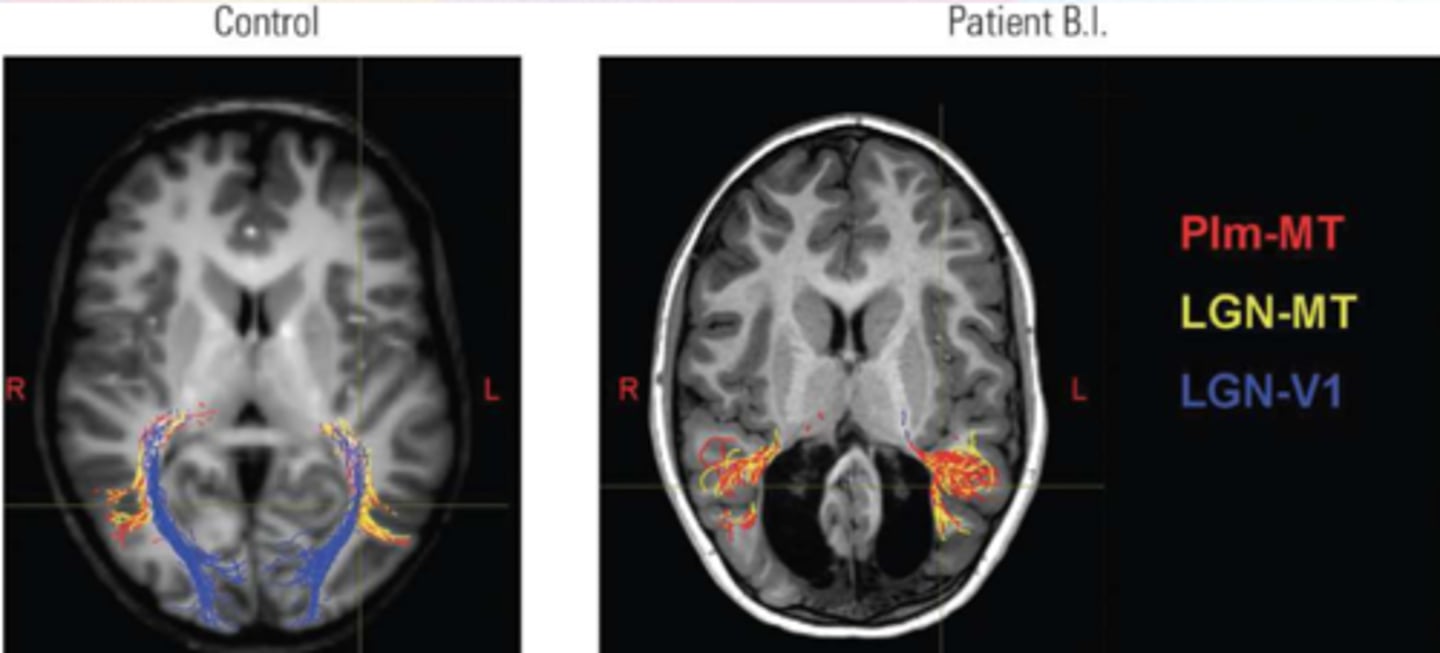

B.I.

More than blindsight

Child sustained damage to the occipital lobe bilaterally in the first 2 weeks of life due to a genetic disorder

At age 6, he is not blind

He can recognize faces and colors, and navigate his environment

Significant plasticity to rearrange his visual system and strengthen pathways from subcortical areas to V5